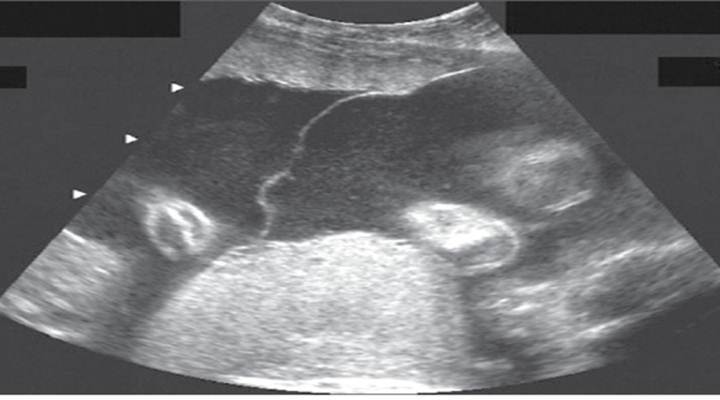

“Double bubble” sign as seen with duodenal atresia